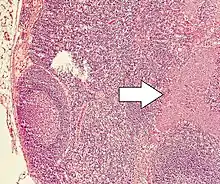

NETs are often small, yellow or tan masses, often located in the submucosa or more deeply intramurally, and they can be very firm due to an accompanying intense desmoplastic reaction. The overlying mucosa may be either intact or ulcerated. Some GEP-NETs invade deeply to involve the mesentery.[72] Histologically, NETs are an example of "small blue cell tumors," showing uniform cells which have a round to oval stippled nucleus and scant, pink granular cytoplasm. The cells may align variously in islands, glands or sheets. High power examination shows bland cytopathology. Electron microscopy can identify secretory granules. There is usually minimal pleomorphism but less commonly there can be anaplasia, mitotic activity, and necrosis.